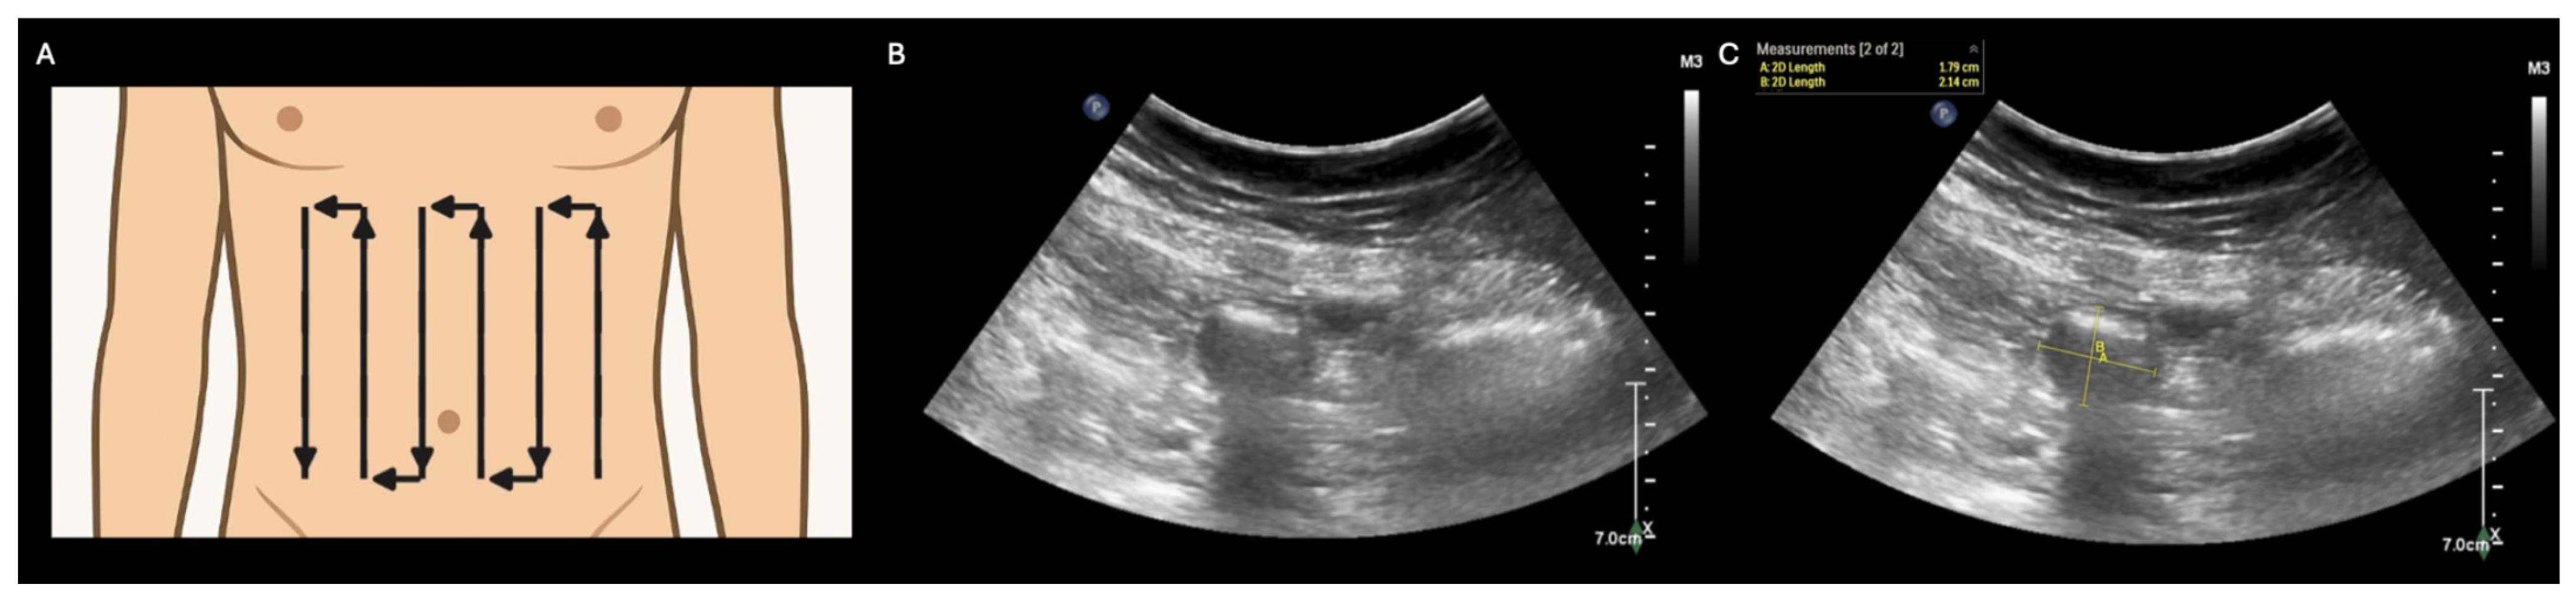

Abdominal pain and/or distension are common presenting complaints in a variety of clinical settings [1,2,3,4]. Traditionally, identifying the etiology of these signs/symptoms has required imaging modalities that utilize ionizing radiation (e.g., X-ray or computed tomography). However, these modalities have significant limitations, including but not limited to the need for patient transport (sometimes including inter-facility transfer) [5] and an oncologic risk to patients [6,7]. These limitations could be avoided by an imaging modality that can both be performed at the point of care and avoids ionizing radiation. Fortunately, point-of-care ultrasound (POCUS) of the GI tract is emerging as just such a bedside tool. While GI POCUS currently lacks the diagnostic accuracy of a CT scan, it may nevertheless help with the initial triaging of GI dysfunction and monitoring the response to therapy over time [8]. This manuscript presents a series of illustrative POCUS images and clips that are representative of important causes of GI dysfunction: ileus, small bowel obstruction, gastric dilation, perforated viscus, and colonic dilation/dysfunction. POCUS screening for GI dysfunction can be performed using a low-frequency (e.g., curvilinear) transducer with a two-phase approach as described by Abramson, et al.: (1) the “lawnmower technique” to scan the anterior abdominal wall systematically, screening primarily for small bowel dilatation (A) and (2) gastric evaluation in the subxiphoid and left upper quadrant regions to screen for gross gastric dilation (Figure 2) [5]. In the first phase of the protocol (A), a low-frequency (typically curvilinear) transducer is used to perform a systematic scan (“lawnmower technique”) across the ventral abdomen, beginning with an initial probe placement in any abdominal quadrant and then the translation of the probe across the abdomen in vertical lines to evaluate the entire anterior abdominal wall and bilateral abdominal flanks. During this systematic scan, the small bowel is examined primarily to assess its (i) diameter and (ii) peristalsis. A normal small bowel has a maximal outer-wall to outer-wall diameter of ≤ 2.5 cm, with values between 2.5 and 2.75 considered borderline abnormal [8] (B,C), and displays waves of peristalsis where the bowel lumen periodically collapses and re-expands (see Supplementary Video S1 for dynamic visualization of small bowel peristalsis).